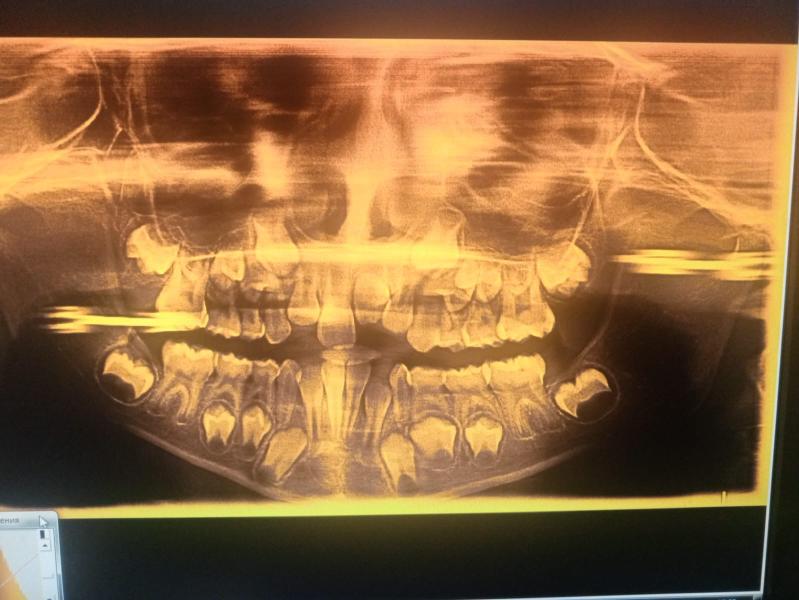

Скрытый кариес у ребенка на панорамном снимке: что делать?

Девочки, вдруг кто то разбирается есть ли у дочки скрытый кариес судя по снимкам?? Панорамный снимок челюсти делали

Я вчера делала кт, чтобы посмотреть на скрытый кариес. Там все видно по другому и сразу ясно что к чему. Вам панораму делали, чтобы кариес посмотреть?